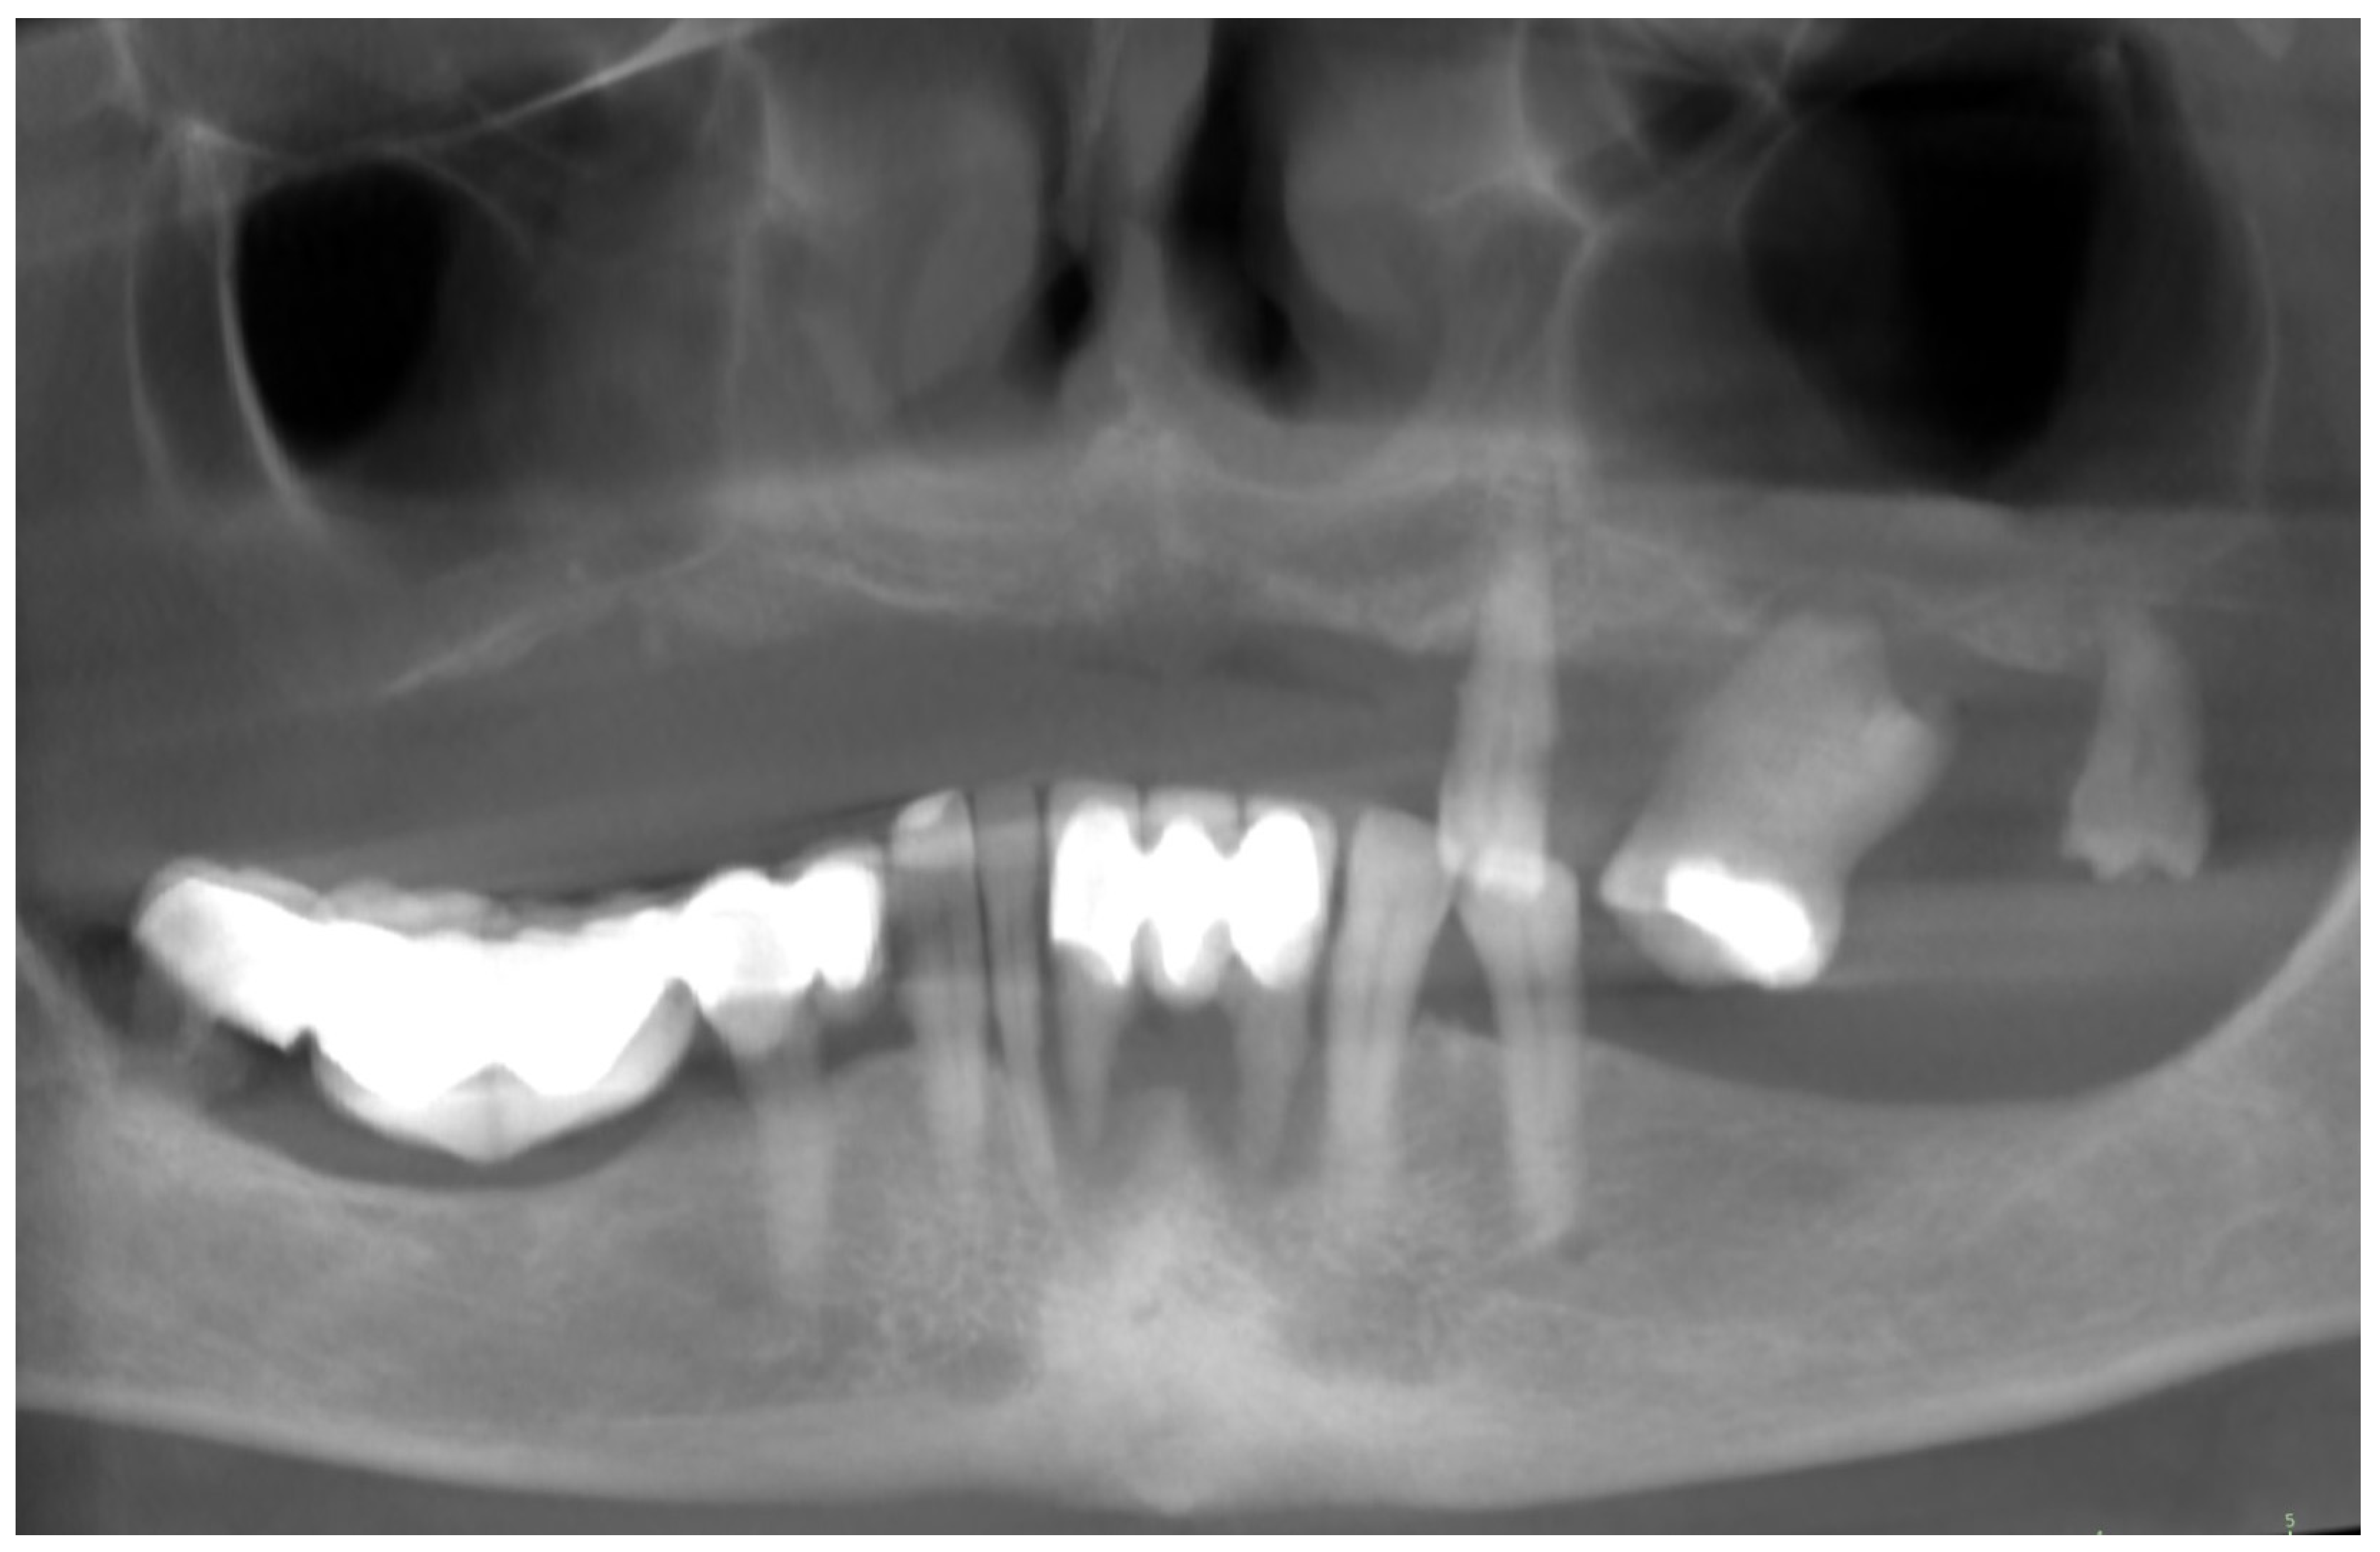

2. Patient Information and Clinical Findings

3.1. Planning and Preparation for the Treatment